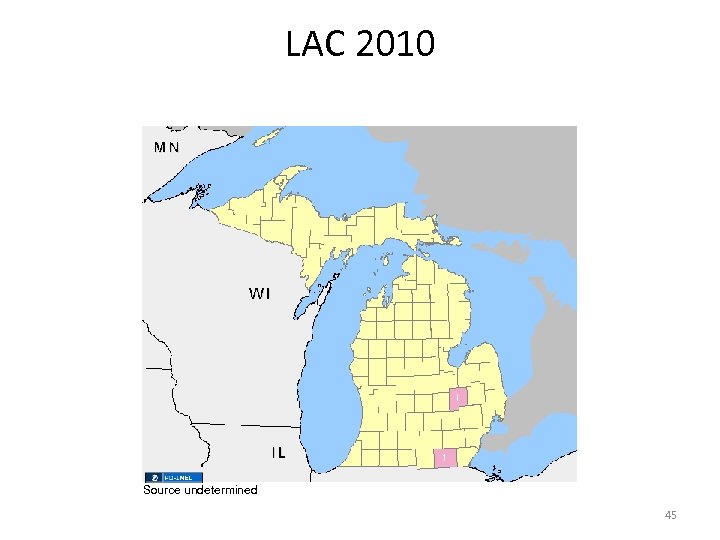

LAC 2010 Source undetermined 45